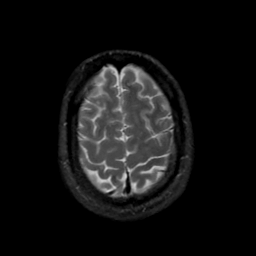

MR Study #17, July 7, 1991 -- Slice #42